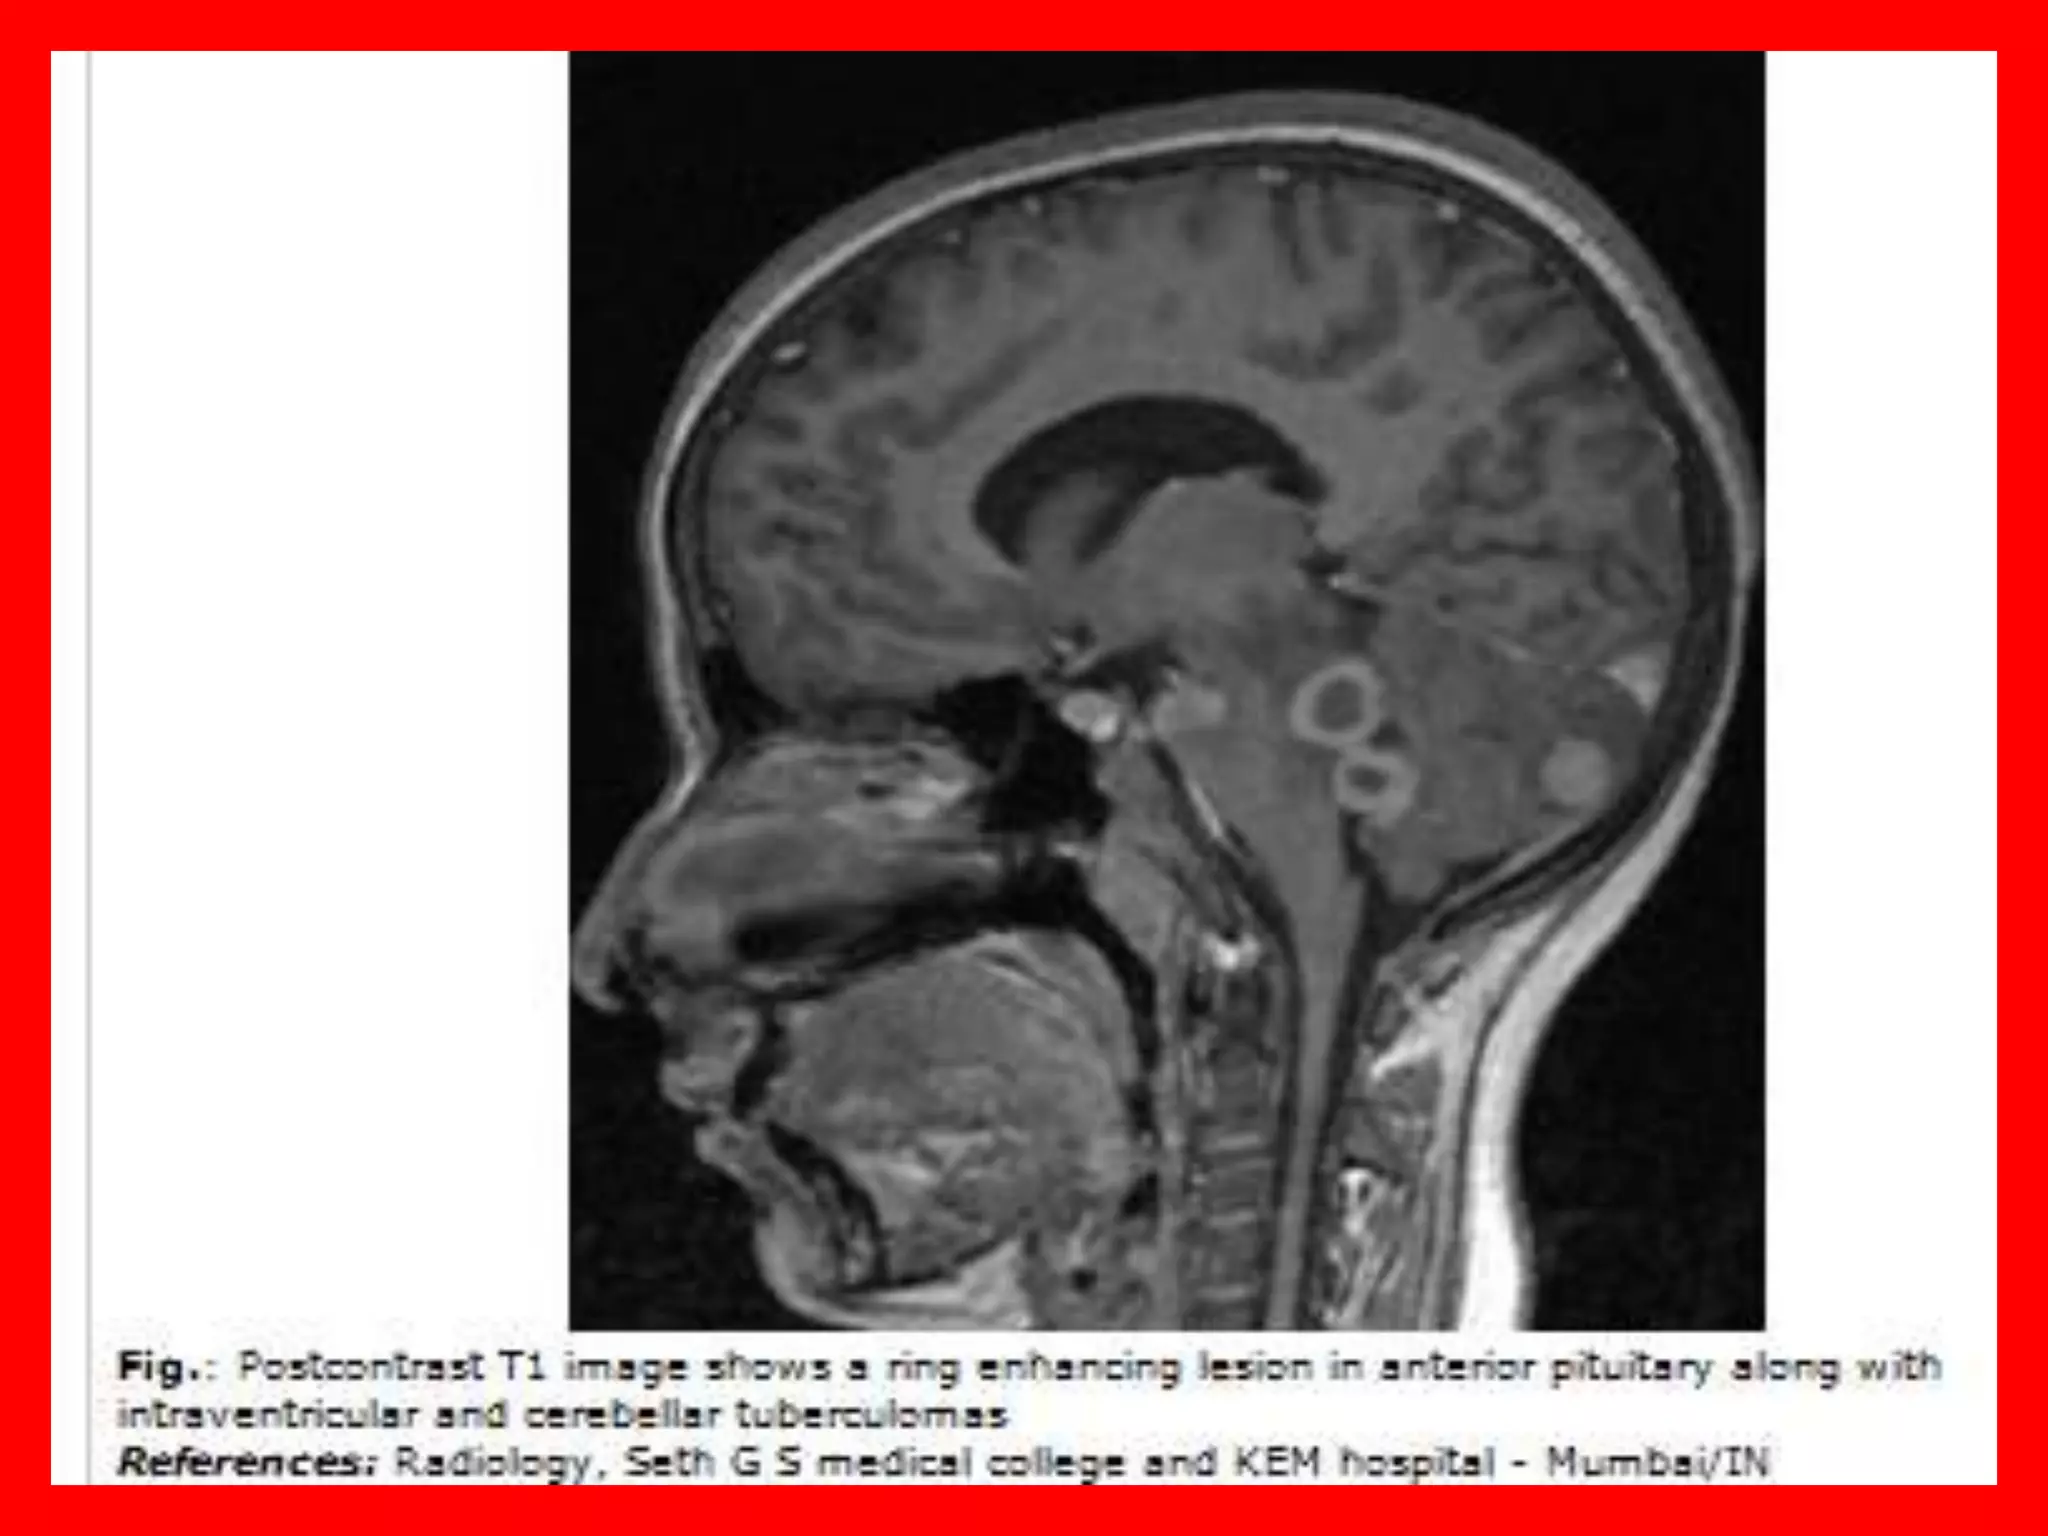

intracranial tuberculoma